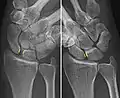

The scapholunate ligament is an intraarticular ligament binding the scaphoid and lunate bones of the wrist together. It is divided into three areas, dorsal, proximal and palmar, with the dorsal segment being the strongest part.[3] It is the main stabilizer of the scaphoid. In contrast to the scapholunate ligament, the lunotriquetral ligament is more prominent on the palmar side.

Complete rupture of this ligament leads to wrist instability. The main type of such instability is dorsal intercalated segment instability (DISI) deformity, where the lunate angulates to the posterior side of the hand.[4][5]

A dynamic scapholunate instability is where the scapholunate ligament is completely ruptured, but secondary scaphoid stabilizers are still preserved;[6] these are the scaphotrapezial (ST), scaphocapitate (SC) and radioscaphocapitate (RSC) ligaments.[6] In a static scapholunate instability, these other ligaments are ruptured as well.